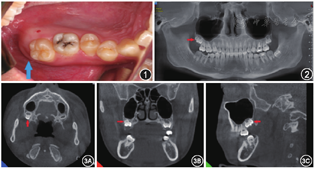

患者,男性,14岁,因发现上下颌阻生牙1周余于2021年7月28日入院。1周前患者因牙列不齐于我院正畸科就诊,给予拍摄CBCT发现右上颌融合畸形牙,制定正畸计划后于我科就诊,要求拔除右上颌融合畸形牙及28、38牙。患者既往健康,否认高血压、糖尿病病史,否认外伤手术史,父母均健康,无类似病史。口腔检查:口腔颌面部左右对称,口腔卫生一般,18、28、38牙口内未见,对应黏膜未见明显异常。17牙正常萌出、27牙舌倾、37牙萌出1/3左右,叩(-),无明显松动(图1)。CBCT示:18牙垂直阻生,牙根未完全发育,18牙冠远中牙尖样突起的牙本质与18牙冠牙本质相通,在横断层面对患牙的根管及髓腔形态进行观察,可预测18牙与其远中牙尖样突起无共同的根管,考虑为18牙与多生牙形成的融合畸形牙。28、38牙垂直阻生(图2, 图3)。

CBCT示:18牙垂直阻生,牙根未完全发育,18牙冠远中牙尖样突起的牙本质与18牙冠牙本质相通,在横断层面对患牙的根管及髓腔形态进行观察,可预测18牙与其远中牙尖样突起无共同的根管,考虑为18牙与多生牙形成的融合畸形牙。28、38牙垂直阻生。

本病例中右上颌畸形牙牙根未完全发育,CBCT显示18牙冠远中牙尖样突起的牙本质与18牙冠牙本质相通,此外,在横断层面对患牙的根管及髓腔形态进行观察,可预测18牙与其远中牙尖样突起无共同的根管。由此,可排除双生牙及结合牙的可能,确诊为18阻生牙与其远中多生牙融合而形成的右上颌融合畸形牙[1]。